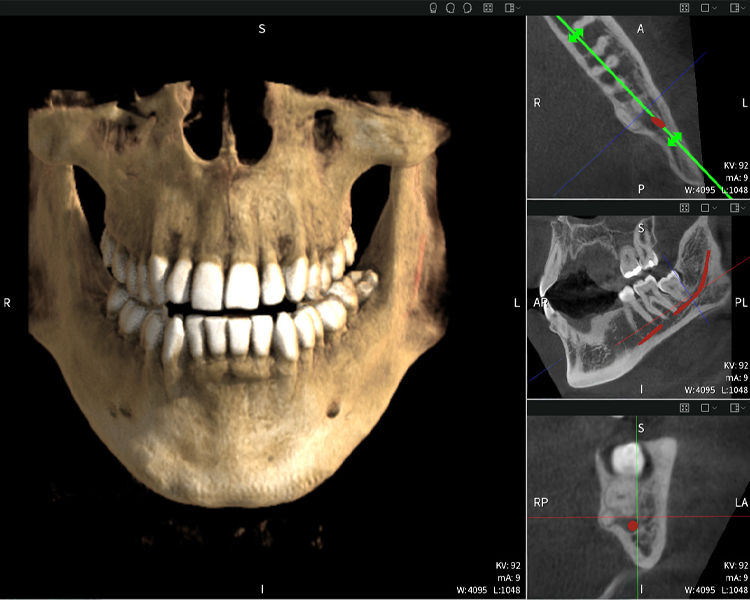

Nachstehend finden Sie einen Fall von Dr. med. dent. Oliver A. Centrella, in dem die CBCT-Aufnahmen mit Seethrough Max entscheidende Informationen zur komplexen Anatomie sowie zur kritischen Beziehung zwischen den Weisheitszähnen und dem Nervus alveolaris inferior lieferten. Bei diesem Fall besteht eine Indikation zur chirurgischen Entfernung der Weisheitszähne.

Abbildungen b–d zeigen verschiedene Ansichten einer 3D-Rekonstruktion des Unterkiefers und bieten eine umfassende Übersicht über die Anatomie des Unterkiefers, die Lage der Nerven im Verhältnis zu den Zähnen und ermöglichen die Beurteilung der Zahnsymmetrie und Ausrichtung.

Abbildung d zeigt den bereits vorbehandelten Zahn 48, dessen Krone entfernt wurde und dessen Wurzeln nahe am Nerv belassen wurden, was das hohe Risiko einer Nervenschädigung verdeutlicht.